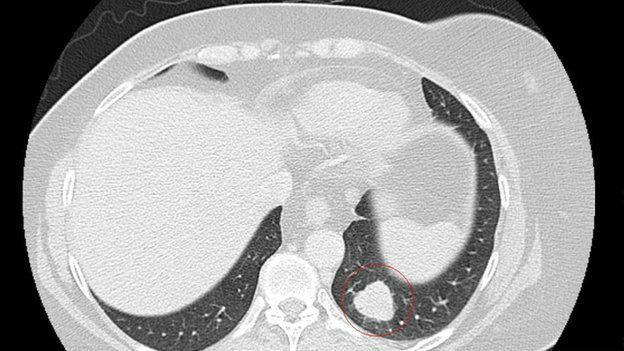

Томограма показує пухлину (обведену червоним) до лікування